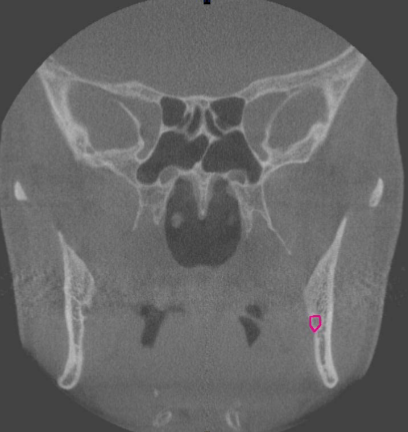

mental foramen (at premolar region)

identify the structure